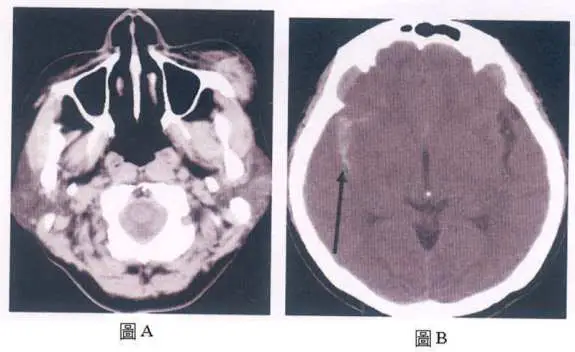

34 歲男性,車禍外傷,劇烈頭痛,意識混亂, CT 影像圖 A可見左臉頰腫脹,根據圖 B箭頭所指的是:

圖 A(顱底層面 CT):

- 顯示顱底切面,可見左側顏面部(左臉頰)軟組織腫脹,符合車禍外傷機轉

- 顱底骨窗顯示可能的顏面骨骨折跡象

- 基底腦池(basal cisterns)部分可見密度增高,提示可能有出血浸潤

圖 B(大腦半球層面 CT)+ 箭頭標示:

- 圖 B 為非顯影劑腦部 CT 橫切面,顯示大腦半球層面

- 箭頭指向腦溝/腦裂(sulci/fissures)內的高密度影,呈細線狀、铸形分布於腦溝之間

- 該高密度影沿腦溝走行分布,不呈新月形(crescent)、不具占位效應(mass effect)

- 此影像特徵代表血液積聚於蜘蛛膜下腔(subarachnoid space),並沿腦溝鑄形分布

- 無明顯局灶性高密度腫塊(排除腦實質出血)

- 無顱骨內板下方的新月形積血帶(排除